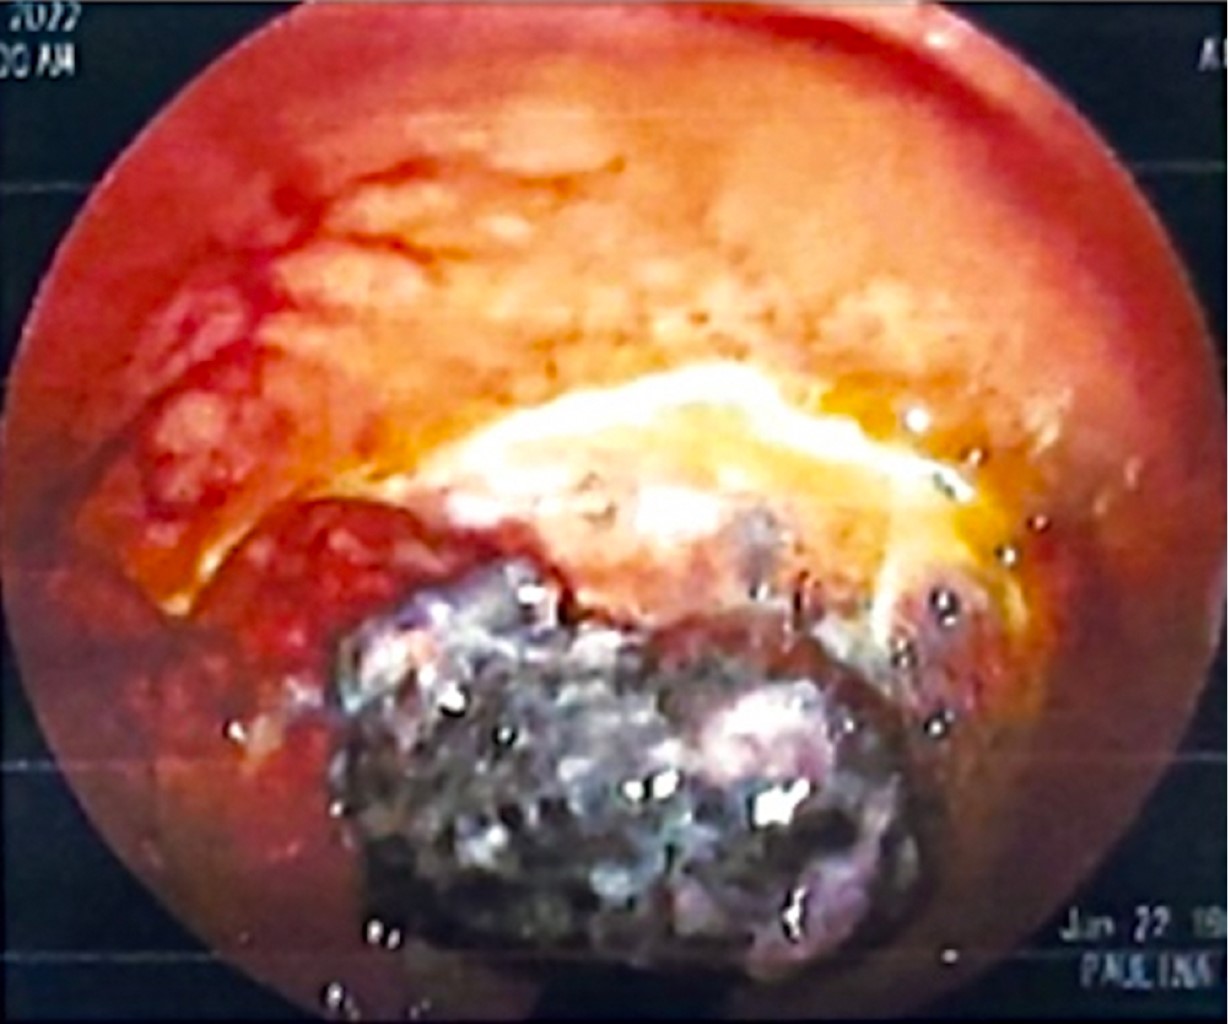

Anorectal melanoma is rare, with 0.4 to 1.6% of all melanomas and 0.5% of anorectal malignancies. Frequently confused with hemorrhoidal disease and polyps. A 53-year-old female with no previous history presented with a foreign body sensation in the anal region and rectorrhagia of two months' evolution. On proctologic examination, an indurated mass was detected in the left lateral region, 4 cm from the anal margin, and an examining glove came out with hematic debris. Colonoscopy reports a 2 cm pedunculated, friable, pigmented lesion located laterally in the dentate line. He underwent a wide local transanal resection (WLTR). Pathology reports malignant melanoma, positive resection margins, and in contact with neoplastic cells. She is subsequently treated with Nivolumab and adjuvant radiotherapy. The surgical options are WLTR and abdominoperineal resection (APR). Traditionally APR was considered the best option for locoregional control of the disease. However, recent studies report no difference in survival compared to WLTR. Most patients are diagnosed late in the disease; therefore, curative surgery is impossible.

Figure 2